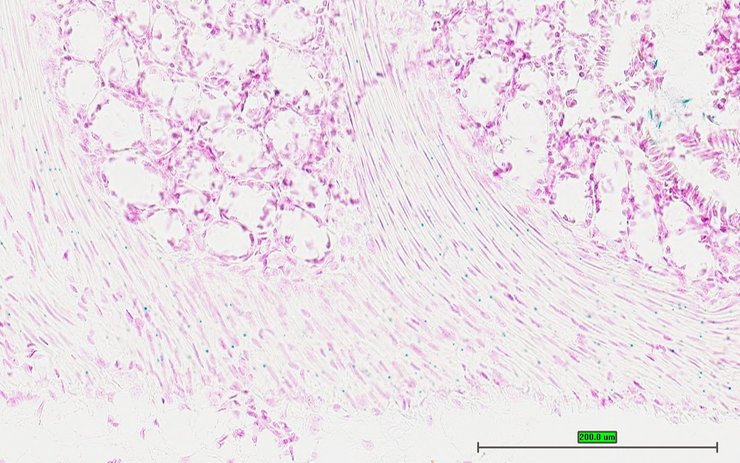

TS28: ductus deferens Present UC Davis_1877368 vas deferens